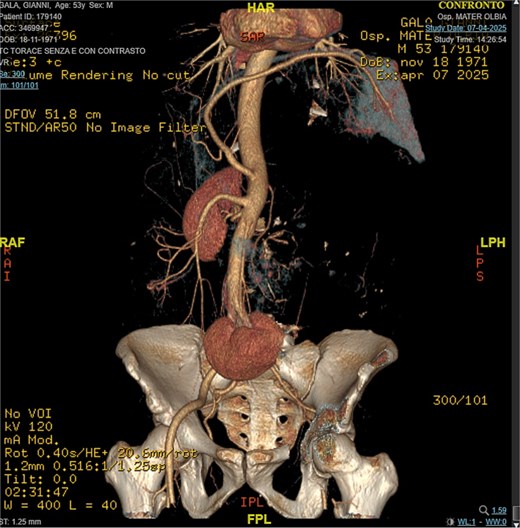

A 53-year-old man, ex-smoker and occasional alcohol consumer, reported several months of postprandial dyspepsia and increased bowel movements (3–4 per day), without weight loss or systemic symptoms. Physical examination revealed a distended, somewhat tense abdomen without focal tenderness. Laboratory tests, including complete blood count, biochemistry, and inflammatory markers, were within normal limits. Cross-sectional imaging demonstrated a multilobulated, predominantly solid retroperitoneal mass measuring 35 × 32 × 18 cm. Contrast-enhanced computed tomography (CT) and magnetic resonance imaging (MRI) showed displacement—but no frank invasion—of the inferior vena cava and aorta, encasement of mesenteric vessels, and compression of bowel loops. A notable anatomic variant was an ectopic left kidney located in the right paramedian pelvis. No distant lesions were identified (Figs 1 and 2). Three-dimensional CT angiography delineated the relationship with major vessels and aided operative planning (Fig. 3). After multidisciplinary discussion, primary surgical resection was favored given the well-circumscribed nature of the mass, the absence of metastatic disease, and the patient’s symptoms. Through a midline xipho-pubic laparotomy, a well-encapsulated, firm, tan-white mass occupying most of the retroperitoneal cavity was exposed. Sharp and blunt dissection allowed complete en bloc excision without capsular violation. Estimated blood loss was modest and no vascular reconstruction was required. Grossly, the specimen weighed approximately 12 kg and showed multinodular architecture with focal myxoid areas.

This case highlights diagnostic and management challenges posed by deep-seated fibroblastic tumors in the retroperitoneum. The retroperitoneum is a prototypical site for primary sarcomas, particularly well-DDLPS, leiomyosarcoma, and undifferentiated pleomorphic sarcoma; consequently, large masses are often presumed malignant [4]. DFH in deep sites can deviate from classic cutaneous presentations and display increased cellularity, myxoid change, and areas that simulate the dedifferentiated component of liposarcoma, complicating histologic interpretation [1–3]. The stakes of misdiagnosis are high: overcalling a benign lesion as sarcoma can prompt unnecessary systemic therapy or morbid surgery, whereas missing an aggressive sarcoma delays definitive treatment. Contemporary guidance underscores integrating morphology, immunohistochemistry, and, where indicated, molecular testing. MDM2 and CDK4 amplification assessed by FISH or immunohistochemistry supports a diagnosis of DDLPS; their absence, in the appropriate morphologic context, weighs against DDLPS [1, 2, 4]. CD34 expression in DFH is variable and nonspecific, whereas S100 highlights neural and adipocytic differentiation and tends to be negative in DFH [1, 2]. In our case, storiform/meningothelial-like architecture, low mitotic rate, negativity for S100 and SMA, and the clinicoradiologic appearance supported DFH. Imaging was informative: despite massive size, the lesion was well circumscribed and compressive rather than infiltrative, with major vessels displaced rather than invaded. From a surgical standpoint, the goal is complete macroscopic resection with an intact capsule and negative margins while preserving function, akin to principles used in retroperitoneal sarcoma surgery [4]. Preoperative three-dimensional vascular mapping aided planning and helped avoid vascular reconstruction. Given the benign biology, adjuvant radiotherapy or systemic therapy is not indicated after complete resection. Because deep-seated DFH may recur after incomplete excision, interval imaging (e.g. CT or MRI) in the first 2–3 years is reasonable, then symptom-driven thereafter, aligning follow-up with lesion size, location, and margin status. Recent reports continue to clarify the spectrum of DFH in unusual anatomical sites and reinforce the importance of targeted immunohistochemistry and, when necessary, molecular assays [1–3]. Advances in retroperitoneal sarcoma care emphasize how precise classification informs treatment selection and follow-up, underscoring the value of multidisciplinary review for large retroperitoneal masses [4, 5].